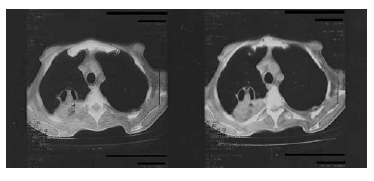

Figure 2. A thoracic computed tomographic scan reveals bilateral nodular lesions with a halo sign, consolidated areas, and a cavitation in the superior lobe of the right lung.

Signs of acute rejection were observed during the third posttransplant month in a 47-year-old man who, at our institution in September 2007, received an orthotopic heart transplant as treatment for dilated cardiomyopathy. This patient’s laboratory test results were seronegative for CMV during the pretransplant period, but the CMV serologic status of the donor was unknown. The patient was treated with cyclosporine (15 mg/kg) and mycophenolate mofetil (2 × 1.5 g) and received prophylaxis against CMV (intravenously administered ganciclovir (2 × 5 mg/kg induction treatment for 2 weeks and 2 × 2.5 mg/kg maintenance treatment) for 1 month and oral valganciclovir (2 × 450 mg) for 2 months as a standard posttransplant regimen. To treat rejection, he received pulsed steroids, a few days after which dyspnea, cough, purulent sputum, and a fever of 38.5ºC developed. The patient was diagnosed as having pneumonia, and treatment with ceftriaxone (1 × 2 g intravenously administered) was initiated. That initial treatment was replaced with piperacillin-tazobactam (4 × 4.5 g intravenously administered) anti¬biotic therapy because tachycardia (102 beats/min), tachypnea (22 breaths/min), and fever persisted, and the patient’s orientation and ability to cooperate deteriorated. The results of biochemical testing revealed the following values: white blood cell count, 5.1 × 109/L; hemoglobin value, 8.3 mmol/L; platelet count, 14 × 109/L; aspartate transaminase, 74 U/L; alanine transaminase, 46 U/L; alkaline phosphatase, 2972 U/L; γ-glutamyltransferase, 803 U/L; L-lactate dehydrogenase, 2177 U/L; total bilirubin, 61.1 µmol/L; and direct bilirubin, 44.3 µmol/L. Treatment with ganciclovir 2 × 5 mg/kg was added to the regimen because the patient exhibited bicytopenia; elevated liver enzymes; cerebral symptoms; and the following values: CMV pp65 antigen, > 8 antigen-positive cells/2 × 105 peripheral blood leucocytes; and CMV real-time polymerase chain reaction results, 31 245 copies/mL, all of which indicated CMV infection. Bronchoscopy was not performed because of the patient’s severe thrombocytopenia, and the histopathologic findings did not confirm CMV pneumonia. Extended spectrum beta-lactamase–producing Klebsiella pneumoniae was grown in the sputum culture, and piperacillin-tazobactam was replaced with carbapenem Meropenem (3 × 1 g intravenously administered). Despite treatment with ganciclovir and the meropenem, the patient required increasing support with oxygen and exhibited progressive dyspnea. A posteroanterior radiograph of the chest revealed pulmonary infiltration and a cavitary lesion in the superior lobe of the right lung (Figure 1). A thoracic computed tomographic scan showed bilateral nodular lesions with a halo sign, consolidated areas, and a cavitation (23 × 19 mm) in the superior lobe of the right lung (Figure 2). Coinfection with Aspergillus was suggested by the thoracic computed tomographic findings, and a galactomannan antigen index of 2.3 supported that diagnosis. Blood samples for serum galactomannan antigen levels were obtained 6 hours after the last administration (and just before the next administration) of the piperacillin-tazobactam infusion to prevent possible false-positive results. The patient was diagnosed as having probable invasive pulmonary aspergillosis and received parenteral voriconazole (a 2 × 6 mg/kg loading dose followed by a 2 × 4 mg/kg maintenance dose). His dyspnea, fever, and biochemical parameters were within normal limits at follow-up. Treatment with the meropenem was discontinued after 2 weeks and ganciclovir therapy was terminated after 4 weeks as the test results for CMV pp65 antigen and the CMV real-time polymerase chain reaction became negative. At the follow-up examination, the patient’s galactomannan levels had also decreased (Figure 3), and a control thoracic computed tomographic scan revealed the decreased dimensions of the nodules and cavity, the regression of parenchymal consolidation, and the resolution of the air-crescent sign in the cavitation (Figure 4). The radiologic findings are shown in Figure 2. The patient’s antifungal treatment was changed to oral voriconazole (2 × 200 mg), which was continued until all abnormal radiologic findings had resolved.